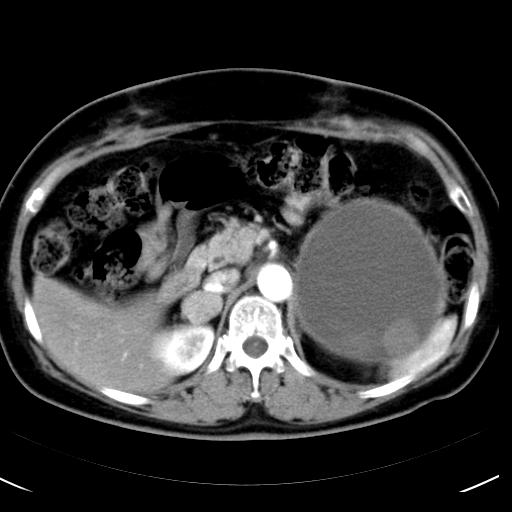

No.42症例2:54歳 女性

紹介された他院にて後腹膜に大動脈に浸潤する腫瘍とのことで開腹したが、腫瘍摘出困難と判定され、本院外科に紹介された。

CA19-9が22030、CEAが82.8と高値。

左側腹部の嚢胞性腫瘤の辺縁はSUVmax6~9

• 図1 腹部CT造影早期相